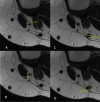

Purpose: The aim of this study is to describe and validate a simple and reliable method to pre-operatively predict the size of the ACL graft in the double strand technique with autologous semitendinosus-gracilis tendons on the same MRI used for ACL rupture diagnosis.

Results: Overall, the median predicted graft diameter from MR imaging was similar to the actual graft diameter with no significant differences (n.s.). Regarding the comparison between predicted and actual graft size, concordance was 78/92 (85%, 95% CI 76-91%), with κ = 0.797 which corresponds to a level of agreement defined as "Strong". Tendon sizes calculated on pre-operative MRI were evaluated both with intra-observer and inter-observer reliability demonstrating a statistically reproducible method. The predicted graft was then compared to the reported one with a statistically significant reliability found.

Conclusion: This study can help the surgeons to perform a fast pre-operative planning of an ACL reconstruction for graft selection. If the planned graft with ST and GT is smaller than 8 mm, the clinician can decide to switch to a different type of graft or plan a different graft preparing technique and, therefore, reduce the risk of post-operative ligament re-rupture. The method proposed is reliable and reproducible. The major strength of the planning technique proposed is that it relies on data that are already available for the clinician before surgery, without the need of further analysis.